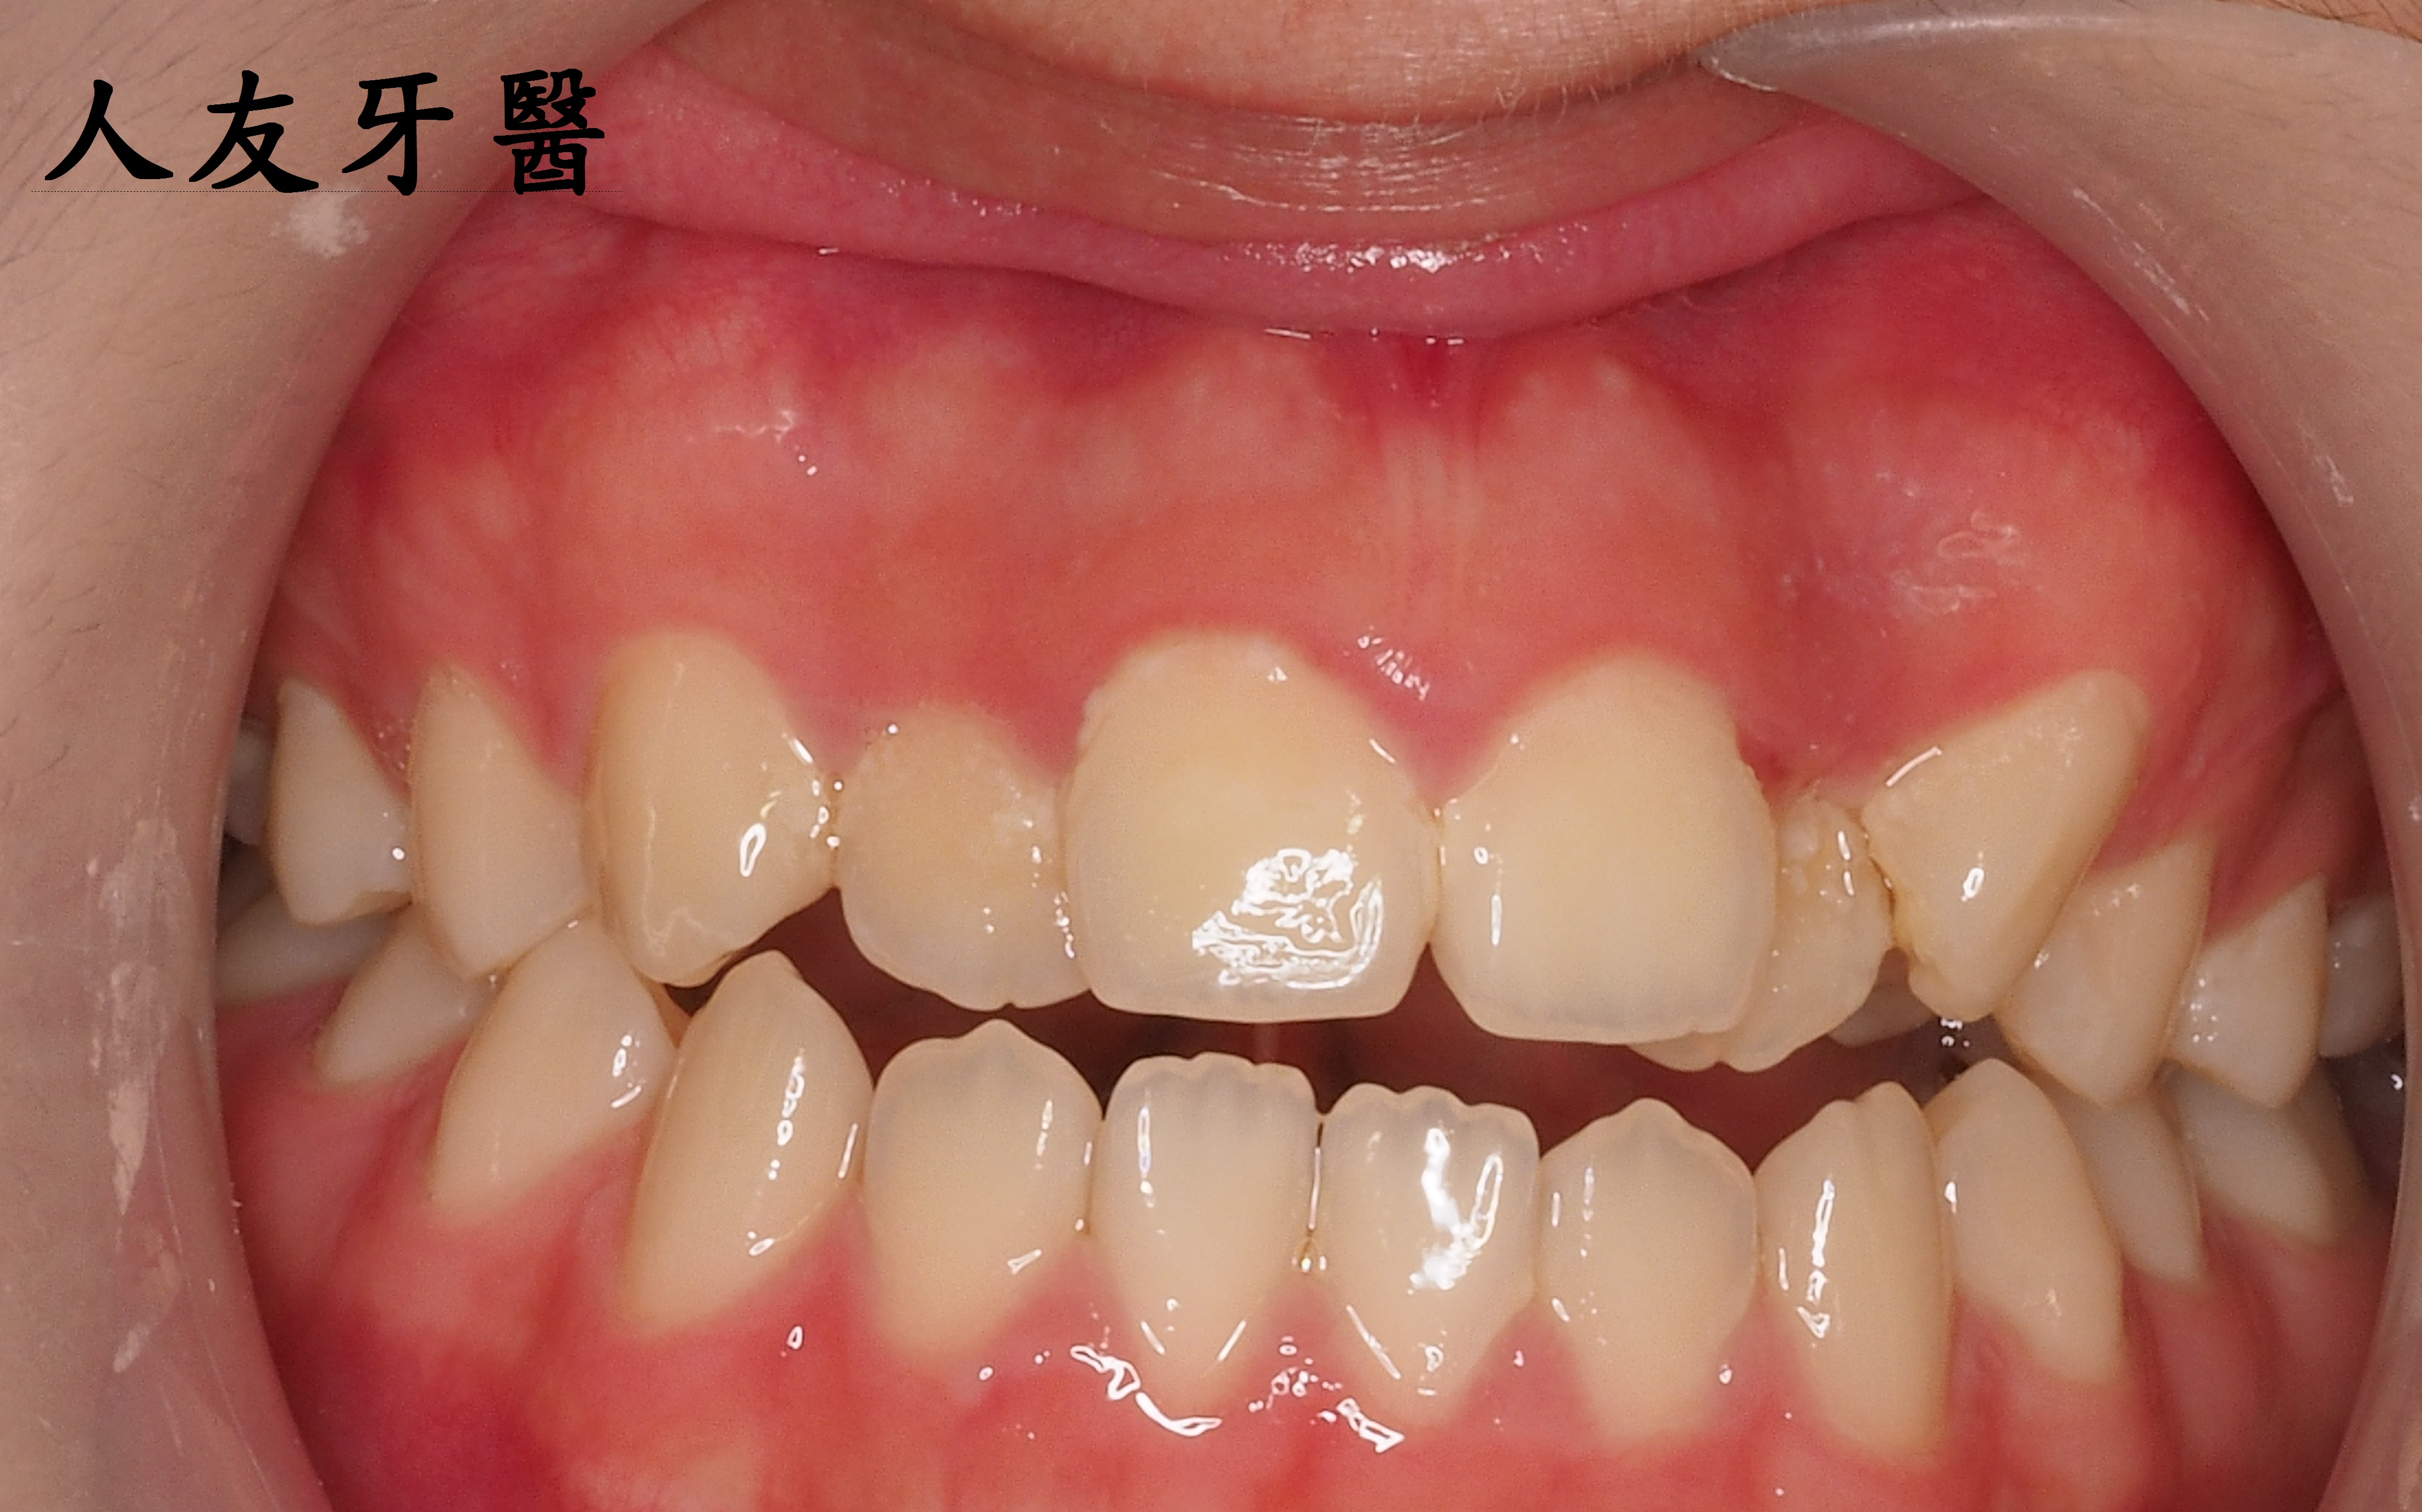

麗質不用天生–嘴唇外凸可以矯正嗎?!

患者陳小姐嘴唇外凸,下門牙分開有一個漏財縫,陳小姐想透過矯正把漏財縫關掉跟改善嘴唇外凸的狀況.

矯正過程中拔掉4顆小臼齒,透過迷你螺絲調整往後拉關縫,讓患者的嘴唇外凸獲得改善,下門牙的漏財縫也關掉了.

而左側門牙根尖有一個病變,醫師透過根管治療的方式把牙根深層的細菌清除乾淨,放入柱心補強,最後再搭配牙套保護.

患者習慣吞口水時舌頭會往前頂,導致暴牙,嘴唇翹翹的,矯正除了把牙齒排整齊,也教導患者如何吞口水練習(吞口水時舌頭要貼在上顎)。

經醫師評估後,可以改善前牙開咬和暴牙情形,需拔除四顆小臼齒,製造空間,上排兩邊需各鎖上一顆迷你螺絲,利用迷你螺絲力量讓矯正器更有效果。

矯正完成後,側門牙裝上牙套

上圖那條紅色線稱為美觀線(E-line)

美觀線是從我們的側臉「鼻子尖端到下巴尖端的連線」,上下唇如果沒有碰到美觀線,在稍微有一點距離的位置,是被認為比較好看的臉型。